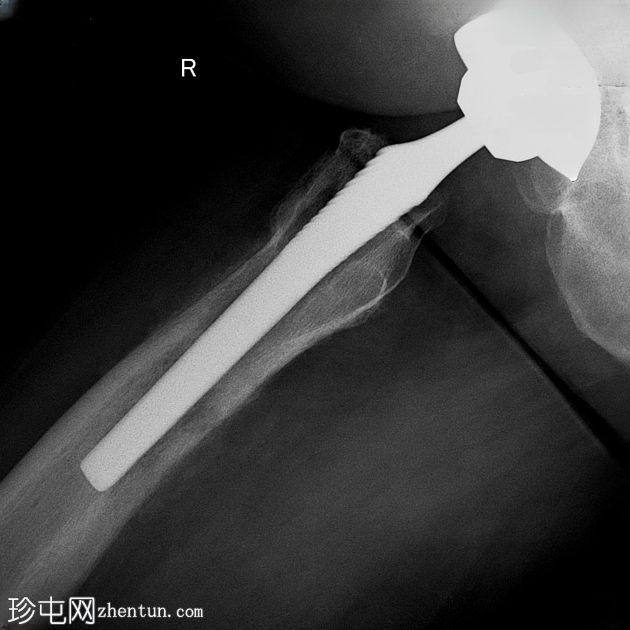

X光片

1.jpeg

正面

右侧股骨骨干近端1/3可见明显的骨皮质变形,并伴有环状骨膜反应。内侧和腹侧表面可见边界清晰的椭圆形透亮区,最大直径约1厘米和2厘米,为骨皮质渗透区。